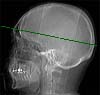

Radioanatomie TDM de l'encéphale avec injection